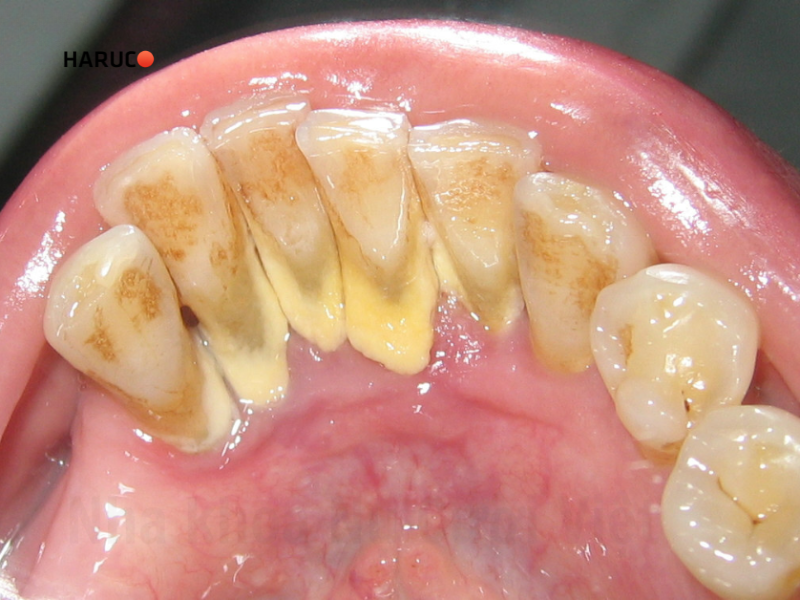

Khi cao răng bắt đầu bong tróc hoặc có cảm giác sần sùi quanh thân răng, đó là dấu hiệu cho thấy vôi răng đã tích tụ với số lượng khá nhiều. Lúc này, bạn nên sớm đến nha khoa để lấy cao răng, nhằm hạn chế nguy cơ viêm lợi, sâu răng hay các bệnh lý răng miệng khác. Bên cạnh đó, duy trì thói quen lấy cao răng định kỳ cũng đóng vai trò rất quan trọng trong việc bảo vệ sức khỏe răng lâu dài.

Trì hoãn lấy cao răng khiến các mảng vôi ngày càng dày, cứng và bám chặt hơn vào bề mặt răng cũng như viền nướu. Khi đó, quá trình làm sạch sẽ mất nhiều thời gian hơn, thao tác phức tạp hơn và nguy cơ gây tổn thương nướu cũng cao hơn. Thậm chí, sau khi lấy cao răng, bạn có thể phải điều trị thêm viêm nướu, dẫn đến tốn kém chi phí và thời gian.